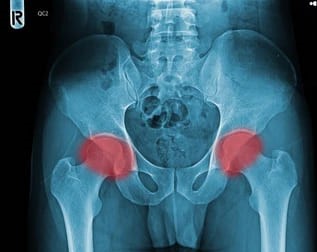

● X-ray(엑스레이)ㅡ 대퇴골두의 모양 변형, 관절 공간의 변화, 뼈 붕괴 여부 등을 확인하는 데 사용됩니다. 하지만 초기 단계에서는 X-ray 상에서 이상 소견이 나타나지 않을 수 있습니다.